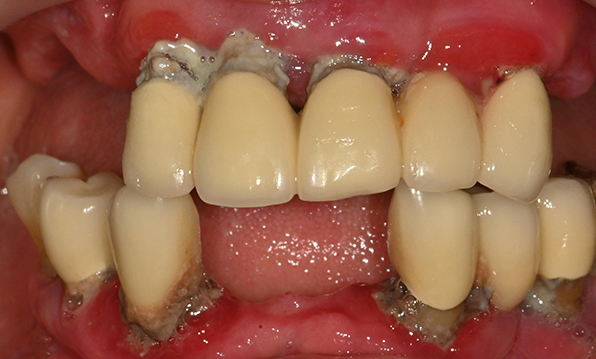

치아가 하나도 남아있지 않거나 전체적으로 상실된 경우 추천합니다.

전체 임플란트가 필요한 경우

치아가 얼마 남아있지 않은 경우

치주질환이 심해, 치아가 있더라도 제 기능을 하지 못하는 경우

전체 임플란트를 해야하는 환자들은

대부분 고령의 환자들로 오랜 틀니 사용

또는 노화로 인해 치조골이

거의 남아있지 않는 경우가 많습니다.

이 때, 치조골 이식을 병행하여 잇몸뼈 재건 후 안정적인 임플란트 식립을 하고 있습니다.